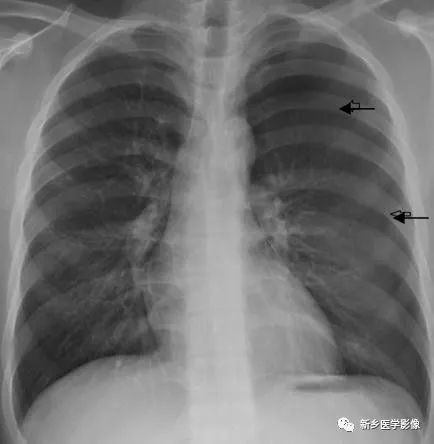

左侧气胸X线胸部正位片图(↑示压缩线)

少量气胸表现为肺向肺门方向压缩,其外侧可见被压缩肺的边缘(气胸线),气胸区域呈均匀、无肺纹理走行的透亮影。大量气胸时,肺向肺门回缩,肺门处可见团块状软组织密度影。患侧肋骨平举,肋间隙增宽,纵隔向对侧移位。CT对少量气胸的诊断、观察要明显优于X线。